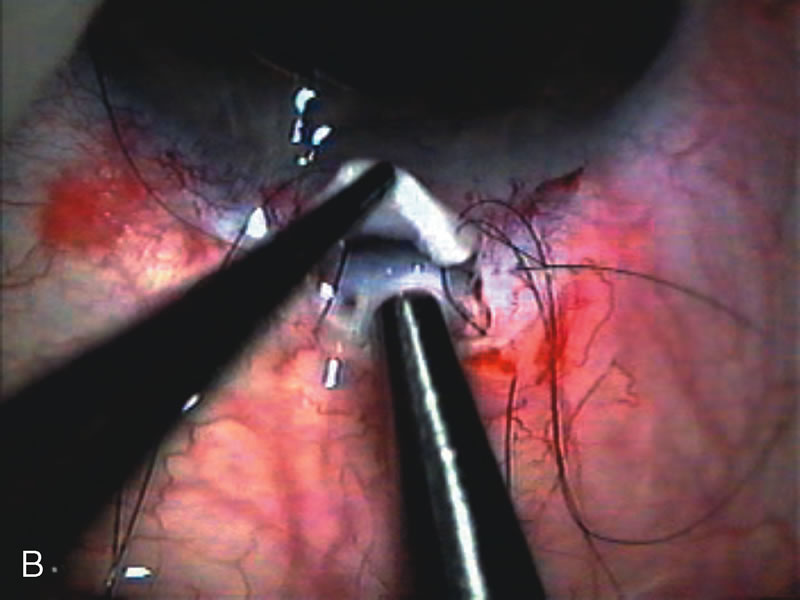

Fig. 1. The anatomic advantage of small incision cataract surgery for the glaucoma patient. A. Long-term bleb function with a large cataract incision is difficult to achieve with either ECCE-trabeculectomy or trabeculectomy followed later by ECCE. This bleb failed to form sufficiently when combined with large incision ECCE. The inflammation, bleeding, and long-term wound healing with stimulation of fibroblasts associated with this technique are more likely to cause bleb failure. In addition, the increased iris manipulation necessary to deliver the nucleus and subsequent iris repair adds to the long-term breakdown of the blood aqueous barrier. B and C. Two-site phacotrabeculectomy has the advantage of small incision cataract surgery combined with separate site trabeculectomy. The incision size is one third the size of the standard ECCE. The inflammation is less severe, and cataract wound healing is confined to the temporal area. Visual rehabilitation with phacoemulsification and foldable IOL is much faster. Phacoemulsification allows successful lens extraction even in the unfriendly environment of a smaller pupil compared with ECCE. The trabeculectomy is performed in an entirely different site, well away from the wound healing associated with temporal phacoemulsification. The likelihood of this filter functioning long-term is greater than with ECCE-trabeculectomy. D. The surgeon also has the option of single-site phacotrabeculectomy with foldable IOL. Both the lens extraction and trabeculectomy are performed through one small 3.5-mm limbal incision.